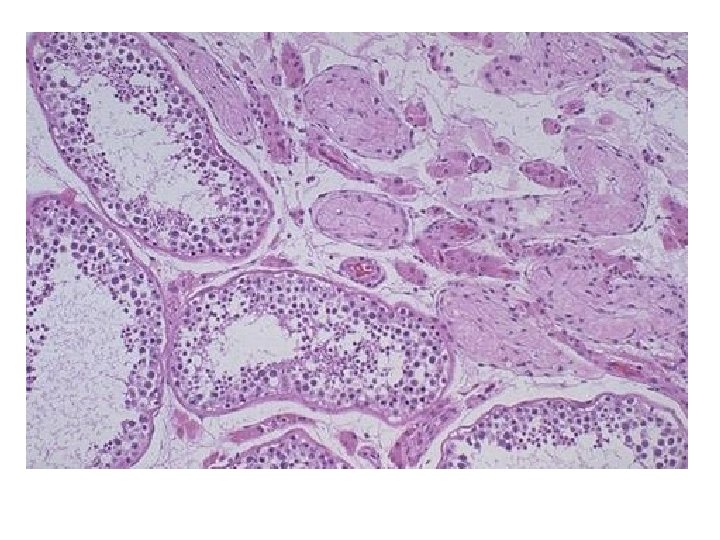

• Kullanılmama atrofisi: Alçıya alınan ekstremitede kas atrofisi ve osteoporoz • Denervasyon atrofisi: Travmatik sinir kesisi • Kan akımı azalmasına bağlı atrofi: İskemi Ateroskleroz ileri yaşta beyin atrofisi • Yetersiz beslenmeye bağlı atrofi • Endokrin stimülasyon kaybına bağlı atrofi: Menopozda endometrium atrofisi, vaginal epitel atrofisi • Senil atrofi: Yaşlanma ile kalp ve beyinde hücre kaybı • Basınç atrofisi: Tümörler çevre dokuya basınç yaparak atrofiye sebep olur.